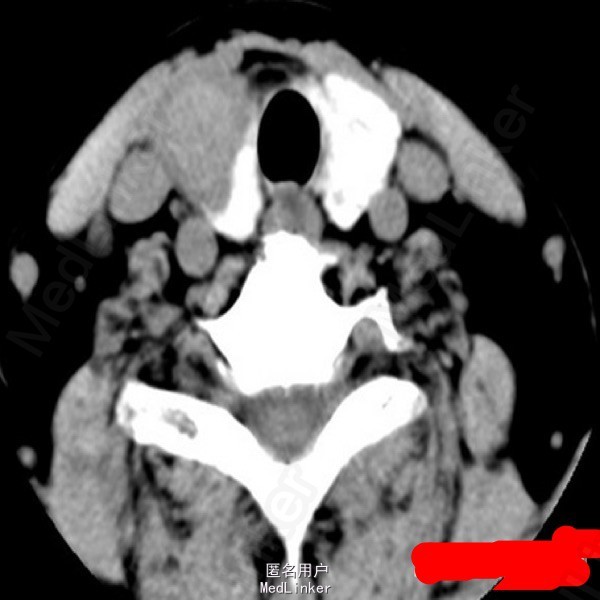

甲状腺癌

中年女性,发现颈部肿物半年,轻度吞咽困难1月。超声提示颈部可见甲状腺低回声结节,内见点状强回声。术后病理:甲状腺乳头状癌。问题:想问问大家对于甲状腺癌术后碘131治疗怎么看?